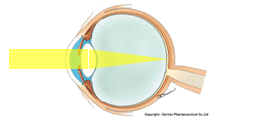

昔のカメラの構造ですが、黒い小さな箱に小さな穴(針穴:ピンホール)を開けて、外からの光が入ってくると、箱の中で反転した映像が、感光剤(フィルム)に当たって写真が写る。という原理があります。

このピンホールカメラ、ちょっと難しいのですが、通常のレンズ光学や、散乱と呼ばれる光の特性と、ちょっと異なり、焦点という概念が当てはまりません。

一般的なカメラは、ピンホールではなく、レンズを使用するのですが、レンズに入った光がフィルムにピッタリと焦点(ピント)があえば、明るく、キレイな画像を得ることができます。

これはピンホールカメラのイメージ図です。太陽からの光が木のてっぺんに当たったとします。通常はそこで散乱と呼ばれる光の広がりが起こり、光が散らばって進みますが、箱の中に入れる光はピンホール(針穴)を通った光だけになるので、木のてっぺんの光は、180度反転して、フィルムの一番下方に当たります。同じように、木の根元からの光は、フィルムの上方の一点に当たります。さらに同様に、木の各部位ごとに、1対1の関係でフィルムに光が当たる構造をとります。

ピンホールと、フィルムの距離が変わっても、基本的には1対1の関係で光が進むことに変わりないため、ピンホールカメラでは、焦点という概念がなく、どの距離のものでも、ある程度はピントのあった画像を得ることができます。